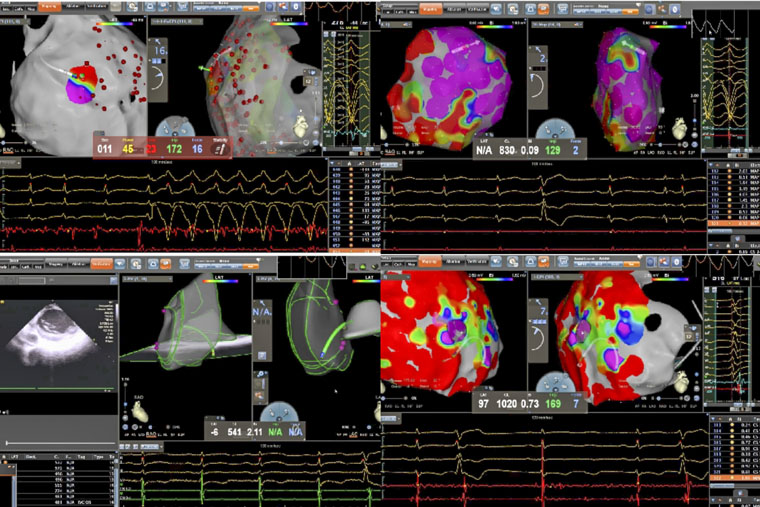

近日,我院心血管内科在马景涛副院长、姚铁柱副主任的指导下,连续完成两例高难度射频消融手术。一例为致心律失常性右室心肌病(ARVC)导致的顽固性病理性室速,另一例为合并贲门癌的左室乳头肌室早消融。两例手术的成功,不仅标志着我院在器质性心脏病相关室性心律失常介入治疗领域实现进一步突破,也突显了多学科协作(MDT)模式在处理复杂危重症患者中的重要价值。

病理性室速通常指由器质性心脏病(如心肌梗死、心肌病等)所导致的室性心动过速。一名患者所患的ARVC,是一种以右心室心肌被纤维脂肪组织替代为特征的遗传性疾病,异常的心肌结构易形成异常电传导通路,从而引发药物难以控制的恶性室速,传统治疗难度大、复发率高。术中,手术团队在X线透视引导下施行心包穿刺,有效规避冠状动脉及心肌损伤风险,为心外膜途径消融建立安全通道。在此基础上,同步进行心内膜及心外膜高密度标测,于右心室多部位识别出低电压区、延迟电位等异常电活动特征,精准判定参与心动过速的关键区域,依托三维电生理标测系统,完成了心内膜与心外膜联合消融。

另一名患者为61岁男性,术前发现频发室性早搏(24小时超过10930次),部分呈三联律及短阵室速,心电图提示起源点为左室乳头肌。频发室早对即将接受大型癌症手术的患者构成多重威胁,如麻醉可能诱发恶性心律失常、室早会影响血流动力学稳定、心脏问题还可能延误肿瘤手术时机。心内科与胃肠外科、麻醉科迅速启动MDT讨论,一致认为必须在肿瘤手术前根除室早这一“定时炸弹”。团队即刻启用“电生理第三只眼”——心腔内超声(ICE)引导手术:ICE导管送入心腔,实时显示左室内乳头肌形态、位置及导管贴靠情况;在ICE引导下克服乳头肌移动难题,实现稳定贴靠与精准消融;ICE实时监测心包情况,极大避免并发症的发生。术后患者室早完全消失,心脏风险解除,并于次日顺利接受贲门癌根治术,现已康复出院。